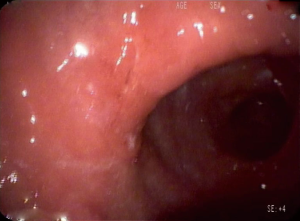

Early stage gastric cancer patients are fit for totally laparoscopic uncut Roux-en-Y gastrojejunostomy after distal gastrectomy. In the present video (Figure 1), the patient is a 61 years old woman who was diagnosed moderately differentiated adenocarcinoma of antrum by gastroscopy and histological test (Figure 2). The tumor stage was assessed to be cT1N0M0 by CT scan preoperation and EUS (Figures 3,4).

Before the day of the operation, endoscopy was performed again in order to confirm the exact location of the tumorand we marked the location of the tumor with nano carbon on the gastric wall.